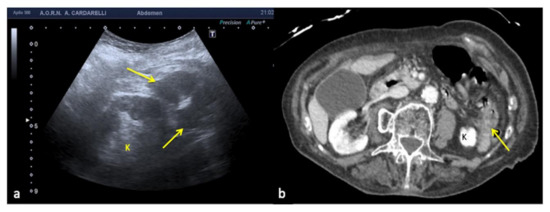

3.4. Anatomy and Anatomical Variants

Some anatomical structures and variances might yield difficult-to-interpret pictures, which can lead to errors if not fully understood [6]. The most insidious in emergency situations are pseudo-splenic hematoma (Figure 16 and Figure 17), pseudo-collections of pleural, pericardial, peritoneal, and retroperitoneal fluids (Figure 18, Figure 19, Figure 20 and Figure 21), and pseudo-pneumothorax related to abolished lung sliding due to the lung pulse or to patient apnea [6,7]. Others, such as hypertrophy diaphragmatic pillar (Figure 22), bladder pseudo-masses (Figure 23), inguinal pseudo-hernias (Figure 24), and the rouleaux phenomena, are generic, random, and highly conditioned (Figure 25). Often it is the emergency condition of the clinical context itself as well as the traumatic accident that could influence interpretational doubts or over-diagnosis with the necessity of more diagnostic confirmations, involving more costly complex examinations, an increased waiting time for the final diagnosis and medico-legal disputes [3,13].

Figure 19. Longitudinal US left flank scan (a) shows at the lower pole of the kidney (K) a hypoechoic area which may be misinterpreted as retroperitoneal free fluid (arrows) in a 22-year-old man investigated for trauma. On CT scan (b) it appears to be a spastic intestinal loop (arrow).